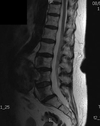

Label this MRI of the spine.

Can see ligaments and discs better

Label the ligaments of this spinal MRI